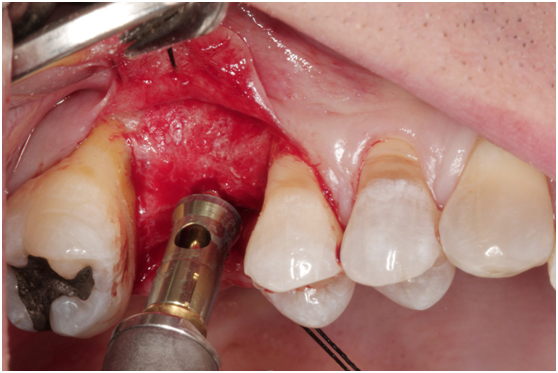

980305幫患者補角化牙齦並翻開清除發炎組織,期待能阻止繼續骨破壞

c. 由98/3補皮的臨床照片,推敲最初原本後面的三顆植體有可能放置在較頰側,但由於鄰接面有足夠的骨頭高度,所以牙齦仍被支撐在恰當位置,因此臨床上無特別發現;但當根裂拔牙後,鄰接面的高度一掉,很快地原本頰側骨頭不足的問題,便很快的浮現出來;接著螺紋跑出,而患者又是牙周病的高風險群,當時身體狀況不佳,口腔衛生照顧不足,都加乘造成骨破壞進一步進行。